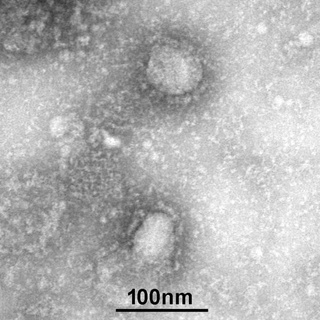

这些飞沫携带着小到人肉眼是不可见的冠状病毒,以至于科学家只能用电子显微镜给它拍照:

病毒身材呈圆形或椭圆形,直径约60-140nm,是一根头发丝的六百分之一。